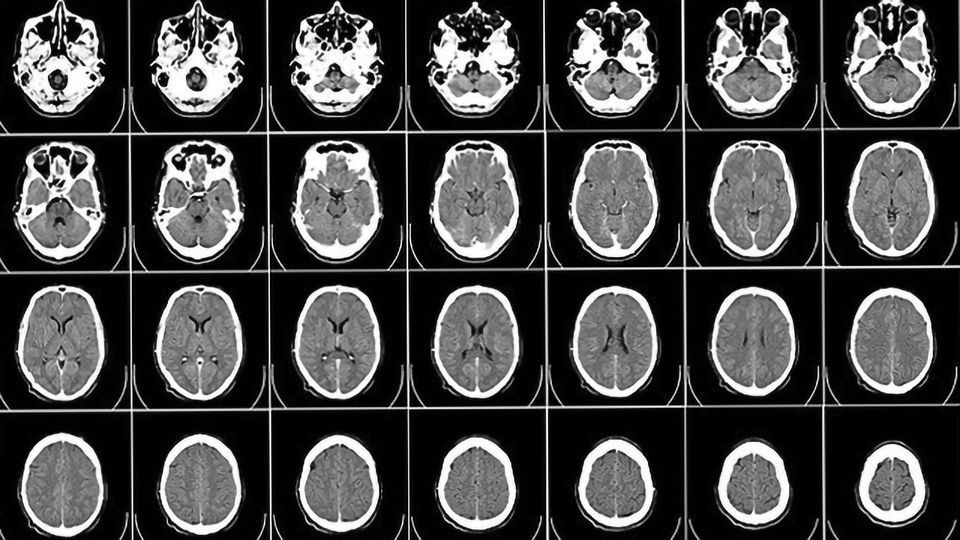

Penggunaan citra medis dalam bidang kedokteran terus berkembang pesat, memberikan pemahaman yang lebih mendalam tentang struktur dan kondisi tubuh manusia. Salah satu teknik yang paling berguna dalam visualisasi citra medis adalah visualisasi 3D. Dalam artikel ini, kita akan membahas tentang visualisasi 3D citra kepala MRI, dengan fokus pada tiga sudut pandang utama: tampang axial, sagital, dan coronal.

Citra kepala MRI (Magnetic Resonance Imaging) adalah salah satu metode pencitraan medis yang paling berharga dalam menganalisis struktur otak dan jaringan sekitarnya. Visualisasi 3D memungkinkan kita untuk melihat citra dalam tiga dimensi, membawa informasi tambahan dan pemahaman yang lebih baik terhadap anatomi dan kondisi pasien.

Tampang Axial

Tampang axial adalah potongan citra yang diambil secara horizontal, sejajar dengan tanah, membentang dari atas ke bawah tubuh pasien. Tampang axial memberikan pandangan detail tentang struktur otak dan jaringan di sepanjang sumbu anteroposterior (dari depan ke belakang). Citra tampang axial sangat berguna dalam mendiagnosis kondisi seperti tumor otak, perdarahan, dan kelainan lainnya yang mungkin terjadi dalam area tersebut.

Visualisasi 3D citra kepala MRI membuka pintu bagi pemahaman lebih dalam tentang struktur dan kondisi otak manusia. Dengan menggunakan sudut pandang tampang axial, sagital, dan coronal, kita dapat menggali informasi yang berharga tentang kondisi pasien dan merencanakan perawatan yang lebih efektif. Teknologi ini terus berkembang, memungkinkan ilmu kedokteran untuk terus maju dan memberikan pelayanan yang lebih baik kepada pasien.

Contoh penerapan visualisasi 3D citra kepala MRI pada tampang axial, sagital, dan coronal ditunjukkan pada video berikut ini: